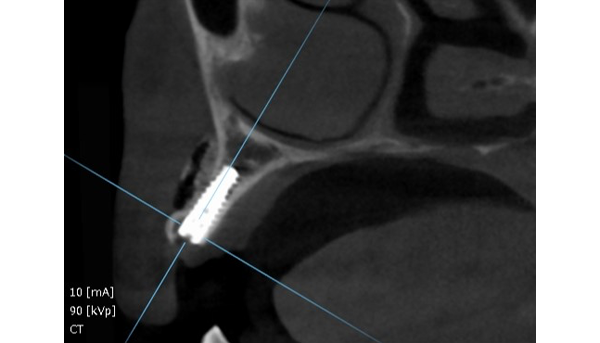

CT画像

「3.7mmという限られた骨幅に、

インプラントを精密に埋め込む技術」

通常、骨の厚みが十分でない場合は治療が難しくなります。

しかし当院では、3.7mm以下という極めて限られた骨幅にも対応できる精密な埋入技術を持っています。

ミクロン単位での位置決めを可能にする専用の診断・手術機器と、豊富な経験を積んだ歯科医師の技術力があってこそ実現できる治療です。

その結果、骨の状態に制約があっても、安全性と長期安定性を両立したインプラント治療をご提供できます。